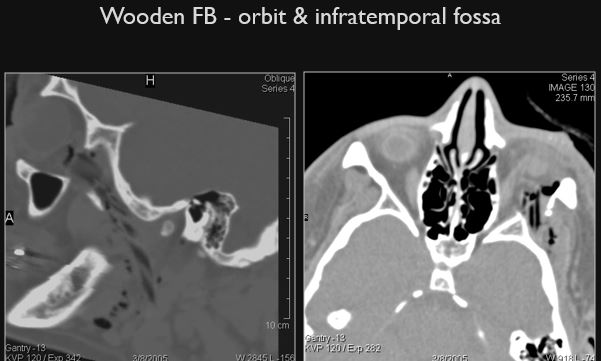

There is an air (low density) pattern, either a tract or “geometrically shaped”, suggestive of a penetrating injury in areas of soft tissue swelling or elsewhere. [Yes/No]

There is one or more “geometrically shaped” low density structures suggestive of a non radiodense foreign body presence. [Yes/No]

The bones of the orbit including the optic canal are abnormal. [Yes/No]

There are other significant abnormalities present. [Yes/No]